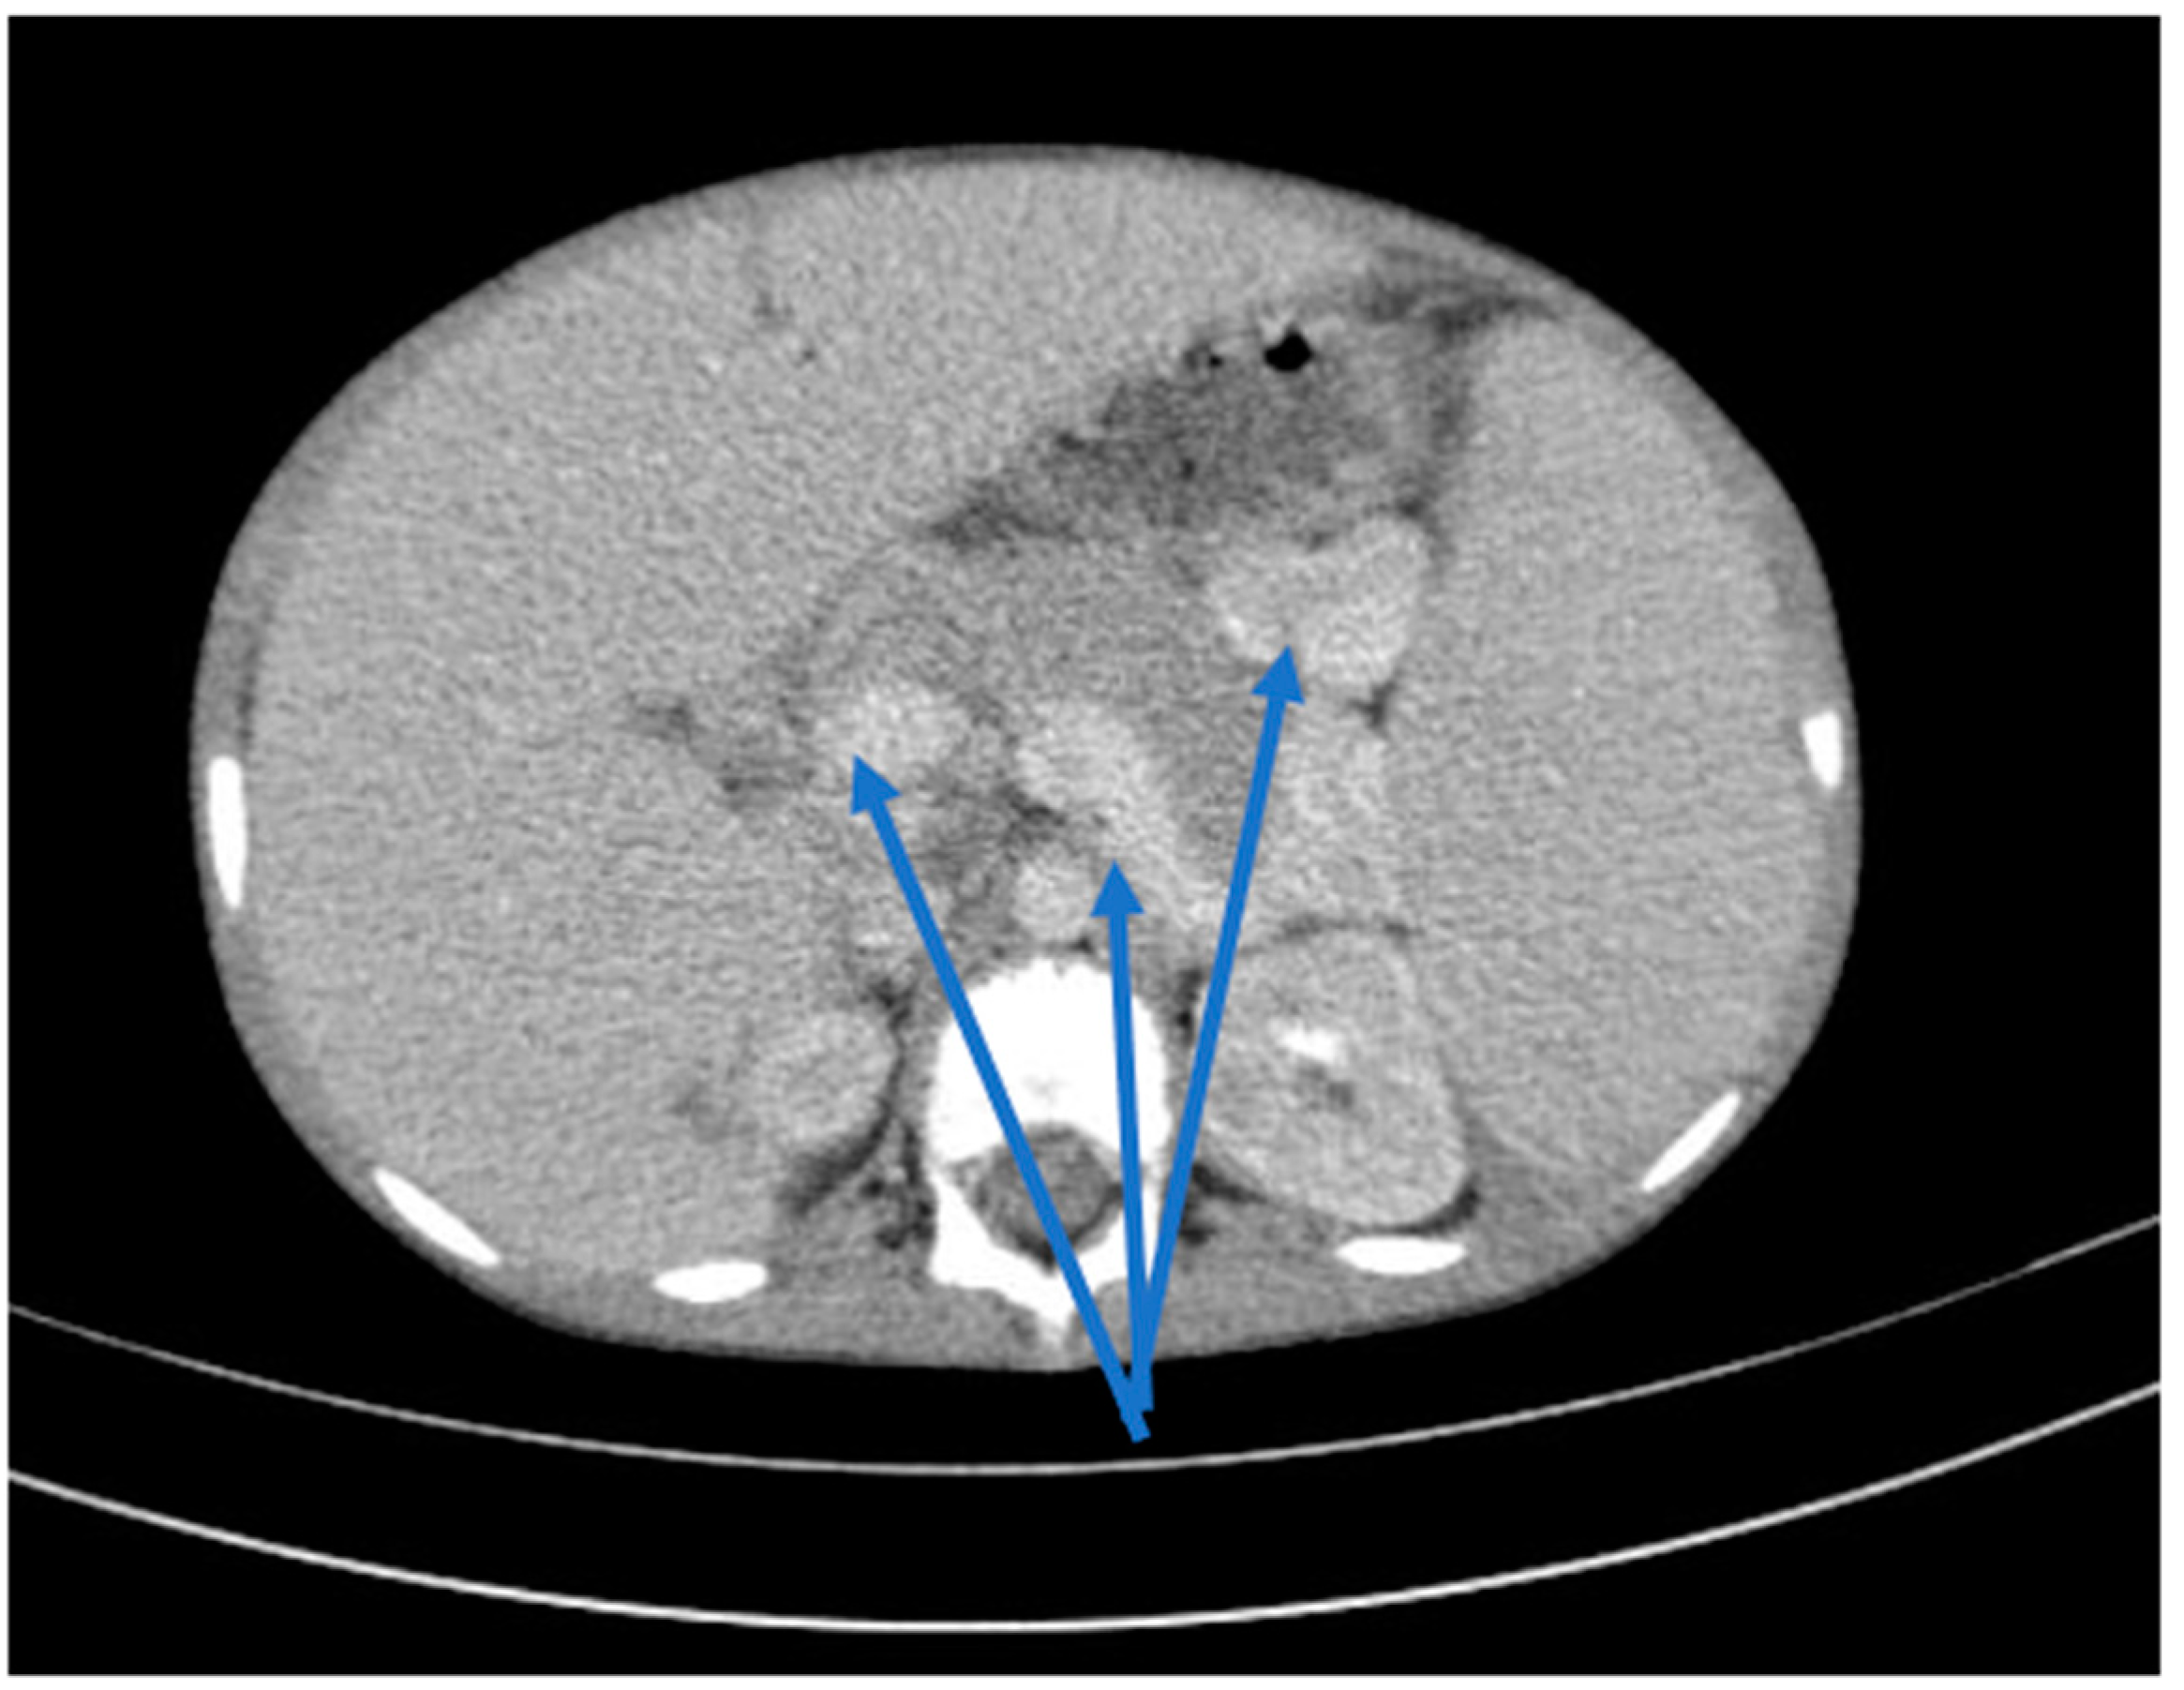

2. Clinical Case